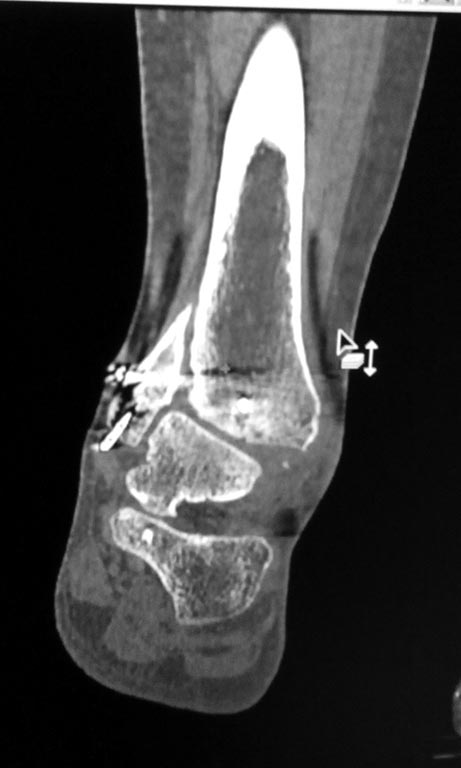

Мужчина, 1987 г.р. получил травму 10.2014. ДТП. Закрытый двухлодыжечный перелом костей костей левой голени, перелом заднего края большеберцовой кости с подвывихом стопы кзади, кнаружи.

Наложен дистрактор. Операция 10.2014: закрытая репозиция, остеосинтез спицами, винтами. В дальнейшем произошло ожидаемое усугубление нарушений взаимоотношений в голеностопном суставе.

Какой план лечения,на Ваш взгляд, предпочтительнее в данном случае? Возможно ли одномоментно устранить подвывих или только на аппарате Иллизарова? Первичные снимки после травмы отсутствуют. Критично ли "растоптана" латеральная суставная поверхность большеберцовой кости?

Мне кажется, что вопрос, поставленный Вами: "Возможно ли одномоментно устранить подвывих или только на аппарате Иллизарова?", отражает не совсем ясное понимание ситуации. Что значит устранить подвывих? А пластику ложных суставов внутренней лодыжки и заднего края большеберцовой кости не нужно делать? И ось голеностопного сустава нужно исправлять. То есть делать остеотомию наружной лодыжки (если она срослась, по снимку не очень понял). Артродез голеностопного сустава в такой ситуации очень сложен. Если же добиться сращения всех переломов в правильном положении, артродез вполне можно отсрочить на несколько лет, что для молодого пациента достаточно важно. Но в конечном счете все определяется Вашим умением и ясным представлением того, чего Вы хотите добиться своей операцией. Во вложении - в чем-то похожий случай. Оперировал эту пациентку 23 лет 11 лет назад через 8 месяцев после похожего на представленный Вами остеосинтез. На первой операции перелом малоберцовой кости в нижней трети был просто не замечен. За счет восстановления оси быстро развившийся артроз протекал благоприятно. В результате артродез был выполнен только в прошлом году, через 10 лет после второй операции. И боли беспокоили пациентку только в течение года перед артродезом.